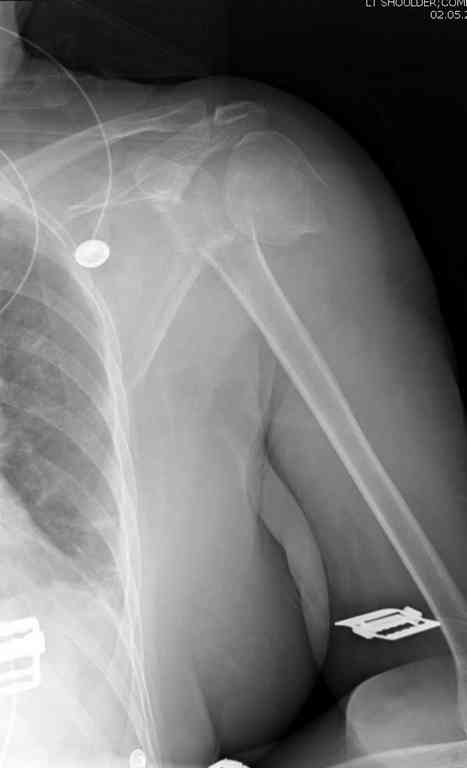

Неправильно выбранная тактика по фиксации или технические ошибки во время операции могут привести к серьезным осложнениям. Здесь привожу

пример из нашей практики, вроде обычный перелом шейки, фиксированный популярным методом "Сиэтла" - множественными спицами 2.8 мм с резьбой на конце.

При первичном осмотре в поликлинике через 3 недели обнаружили миграцию двух спиц, срочно госпитализированному на второй день перед операцией на всякий случай сделали снимок, одна спица находилась под ключицей в шейном отделе (на снимке).